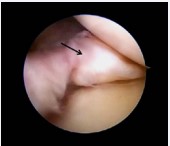

A 44 year old patient, male suffering from rheumatoid arthritis, complaining pain and clamping of the right knee for 5 years during the daily routine activities, with no associated trauma. The patient presents with a history of physiotherapy treatment and two arthroscopic procedures, with no improvement of symptoms. Radiographic examination revealed an image consistent with an intra-articular loose body in the medial compartment, in the topography of the posterior horn of the meniscus (Figure 1). The Magnetic Resonance Imaging (MRI) enabled the identification of bone tissue internal to the posterior horn of the medial meniscus (Figure 2). The surgical treatment was performed by arthroscopy via inter condylar access through the anterolateral and anteromedial portals (Figure 3) to position the optics and visualization of the posterior compartment (Figure 4). We identified the mensicalossicle adjacent to the posterior horn of the medial meniscus (Figure 5) and performed its removal utilizing basket forceps associated with economic resection of the posterior horn of the meniscus, due to the intimate anatomic relation between the two structures (Figures 6,7). The material was subjected to histopathological analysis, which identified fragments of meniscus containing hyaline alterations and metaplastic ossification, apart from a degenerative process, fibrosis, and foci of neovascularization (Figure 8). The patient evolved satisfactorily, with complete recovery of the range of motion and absence of joint locking symptoms, being that his last clinical evaluation was done with 3 months of postoperative. The last X-ray showed the absence of the bone body on the posterior compartment of the knee (Figure 9).

Figure 5: Arthroscopic image of the meniscal ossicle in the posterior horn of the medial meniscus (arrow).